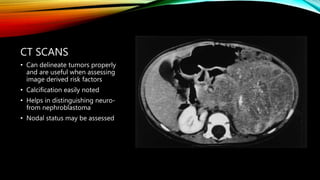

CT SCANS

• Can delineate tumors properly

and are useful when assessing

image derived risk factors

• Calcification easily noted

• Helps in distinguishing neuro-

from nephroblastoma

• Nodal status may be assessed